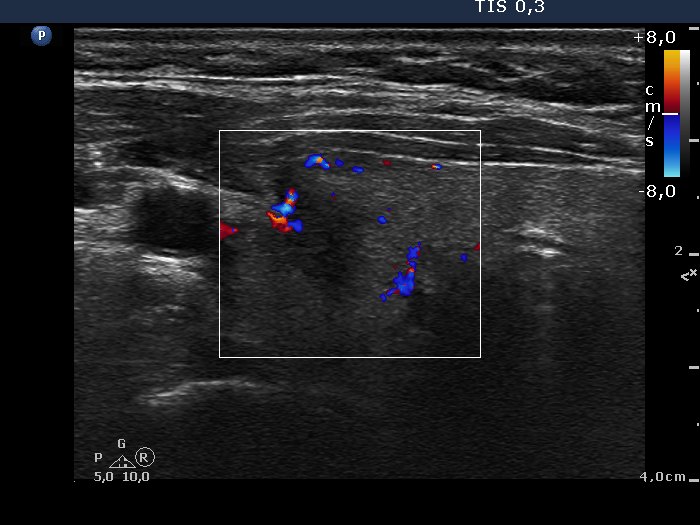

Ultrasonography. The right lobe was minimally hypoechogenic while the left was echonormal. Both lobes contained tiny hypoechogenic areas, the echogenicity index was < 5%. There was a hypoechogenic lesion in the ventrolateral part of the right lobe. The lesion presented irregular, lobulated margins and blurred borders, as well. The intranodular blood flow was increased.

Histopathology disclosed papillary carcinoma in the right nodule with a maximal diameter of 7 mm.

Comment. Histopathology disclosed that the tumor did not reach the capsule. The ultrasound examination was not obvious in this respect, because a small part of the tumor was very close to the edge of the thyroid.